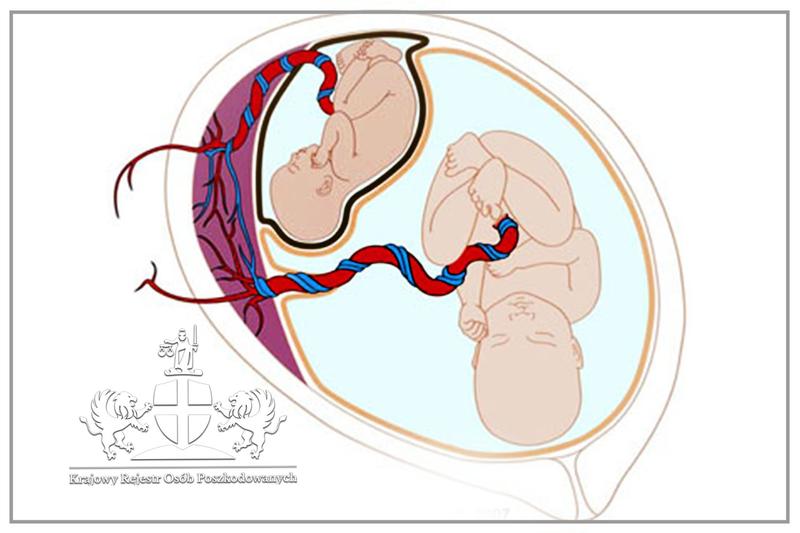

Temat ciąż bliźniaczych od zawsze fascynuje nie tylko przyszłych rodziców, lecz także miłośników różnorodnych ciekawostek. W końcu kto nie chciałby marzyć o podwójnym szczęściu? Choć statystycznie ciąża bliźniacza występuje tylko w jednym na 80 porodów, w ostatnich latach zauważamy znaczący wzrost takich przypadków. Dlaczego tak się dzieje? Z pewnością czynniki genetyczne odgrywają tutaj kluczową rolę. Obecność bliźniaków w rodzinie zwiększa szansę na ich narodziny! Niemniej jednak, nie tylko geny mają znaczenie – istnieją także inne aspekty, które mogą sprawić, że wkrótce w twoim życiu pojawią się dwojaczki.